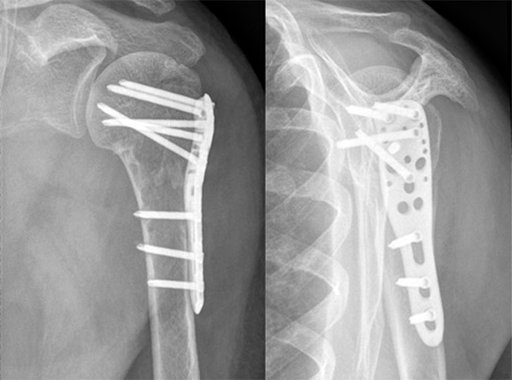

Перелом проксимального відділу плечової кістки синтезований пластиною типу PHILOS